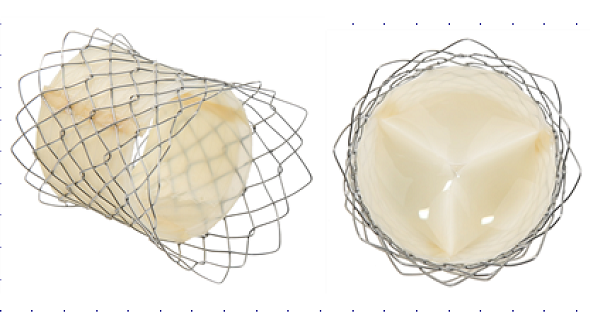

서울의대 김기범 교수(서울대병원 소아청소년), 김용진·임홍국 교수(소아흉부외과)팀이 돼지의 심장 외막으로 만든 폐동맥 인공심장판막을 스텐트 시술을 통해 10명의 환자에게 적용하는 임상시험을 성공적으로 마쳤다.

연구팀이 개발한 자가확장형 폐동맥 인공심장판막과 스텐트는 아직 상용화된 제품이 없어, 현재 한국과 미국, 중국이 시장 선점을 위해 치열하게 경쟁하고 있다.

연구팀은 2004년 보건복지부에서 지원한 바이오이종장기사업단을 통해 돼지와 소의 심장 외막을 이용한 인공심장판막 개발을 시작했다. 그리고 후유증이 큰 가슴을 여는 수술 대신 간단한 시술로 판막을 이식하기 위해 태웅메디칼과 스텐트 개발도 동시에 진행했다.

수년간의 연구 끝에 개발된 판막은 이종이식의 문제점인 면역거부반응이 '0'에 가까운 차별화된 장점을 가졌다. 이를 통해 미국과 중국의 판막보다 우수한 내구성 및 안정성을 확보했다.

최근 인공심장판막 치료는 피부정맥에 도관을 삽입하고 도관을 따라 판막을 감싼 스텐트를 판막 부위에 이식하는 시술이 주목받고 있다.

현재 고령층의 대동맥판막협착증 환자를 대상으로 미국 등 선진국에서 개발된 타비(TAVI)라고 불리는 자가확장형 인공심장판막-스텐트가 상용화돼 있다. 연구팀이 개발한 스텐트와 판막은 폐동맥판막 질환에 특화된 것으로 차별성이 있다.